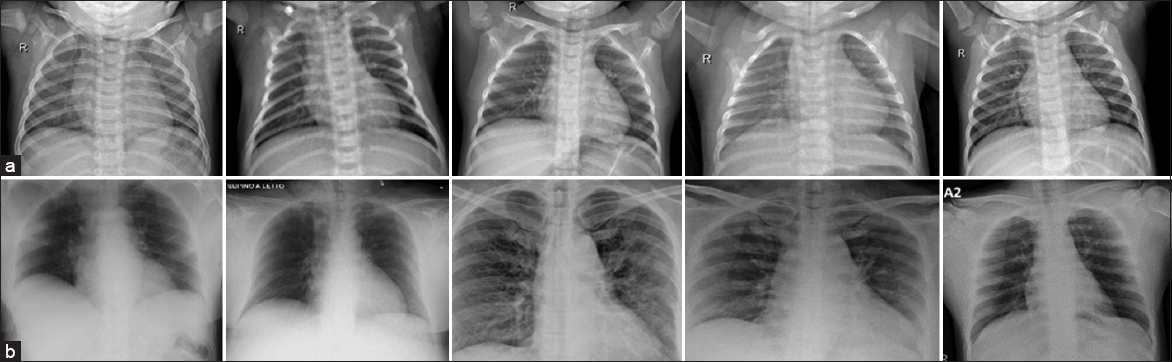

Two sets of X-ray images are used in this approach, as shown in Fig. 2, the first set regarding to normal X-ray images and the second set is abnormal X-ray images. These images are prepared to be ready for the implementation process.

Fig. 2. X-ray images dataset. (a) normal X-ray images and (b) abnormal X-ray images.